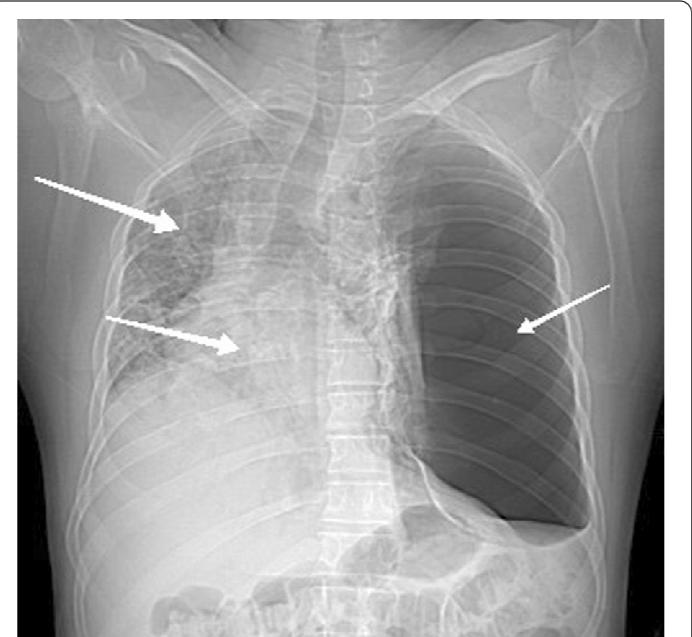

Can you 'dig deep' to spot the sign?

Diagnosis?

Deep sulcus sign

Pneumothorax.

On a supine chest Xray (common in ICUs or as part of a trauma Xray series), it may be the only suggestion of a pneumothorax

👉because air collects anteriorly and basally, within the non-dependent portions of the pleural space, as opposed to the apex when the patient is upright

Patients with chronic obstructive pulmonary disease (COPD) may exhibit deepened lateral costophrenic angles due to hyperinflation of the lungs and cause a false deep sulcus sign.